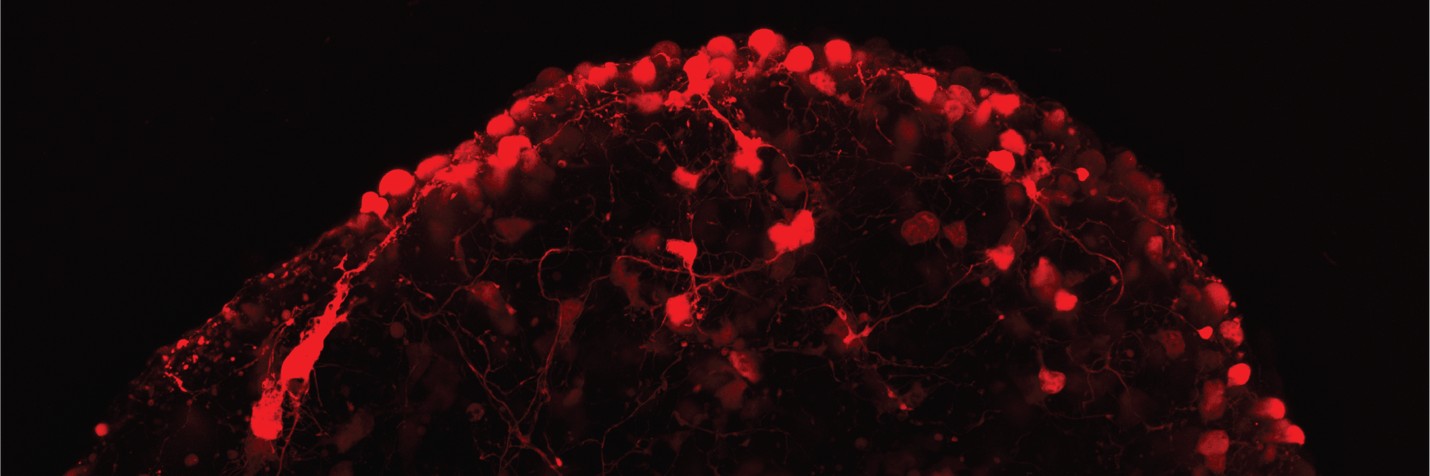

The Neural Engineering for Restoring Vision (NERV) lab studies how the visual system develops, remodels, and can be repaired after injury or disease. We engineer ex vivo and stem cell-derived models of the retina, optic nerve, and retinorecipient targets in the brain to uncover the principles of neuroplasticity. By combining electrophysiology, tissue engineering, and cell transplantation, we are developing tools to study how transplanted neurons integrate into host circuits and using transplantation itself as a strategy to restore vision. Our goal is to translate fundamental discoveries into therapies that promote remodeling, repair, and recovery in the visual system.

- Organoid and organ-chip models – Engineering retinal tissues to study neural circuit formation and donor-host integration